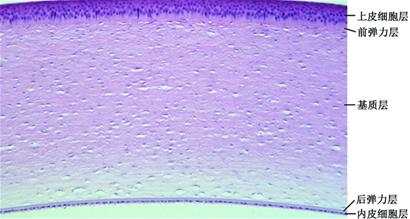

长达9年的科研攻关,一朝透出曙光。昨日,记者了解到,由开云电竞网址角膜组织工程实验室研制的组织工程人角膜内皮(简称人工角膜内皮),已经成功完成兔、猫和猴的角膜移植实验,这在国际上尚属首次,表明角膜中的重要部分之一——角膜内皮已经可以人工“制造”,有望年底或明年初进入临床实验。此外,该实验室已初步获得了人工角膜上皮,下一步计划制造出完整人工角膜。

昨日下午,记者来到位于开云电竞网址的角膜组织工程实验室,据海洋生命学院副院长、实验室主任樊廷俊教授介绍,由该实验室研制的人工角膜内皮,继去年在新西兰兔角膜内皮移植成功后,今年又在家猫和猕猴角膜内皮移植中获得成功。截至昨日,所移植的人工角膜内皮已使新西兰兔角膜维持透明385天、家猫角膜维持透明203天、猕猴已维持角膜透明113天,这在国际上尚属首次!

“这些兔子、猫和猴子,都分别在实验动物中心里面饲养,现在状态都很好。 ”樊廷俊说,实验动物眼睛角膜的内皮层被撕除,然后移植入角膜组织工程实验室自己制造出来的人工角膜内皮,在百天以后,兔、猫和猴的角膜仍然保持透明,攻克了移植人工角膜内皮无法使角膜长期保持透明的国际性难题。记者看到,一只“移膜猫”的眼睛清澈透明,一点儿看不出移膜来。

记者了解到,在造出人工角膜内皮后,樊廷俊和他的研究团队又将目光瞄向了完整人工角膜,他们的研究是在国家科技部“十五”863课题、“十一五”863重大课题和企业委托开发课题的资助下完成的。目前,他们与青岛中皓生物工程有限公司合作,开始了完整人工角膜的制造技术研究,已成功造出人工角膜上皮,计划于3-5年内造出完整人工角膜并完成其动物移植实验。